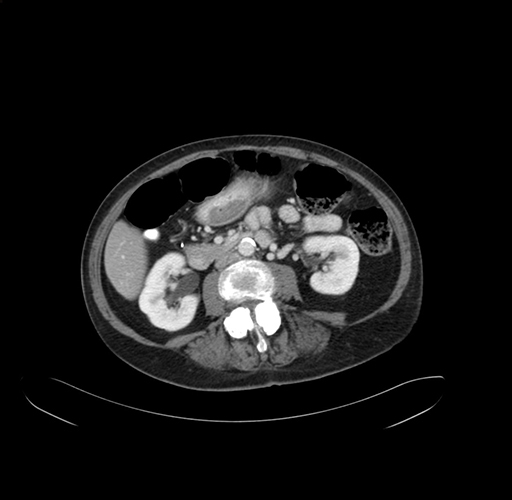

Axial Venous